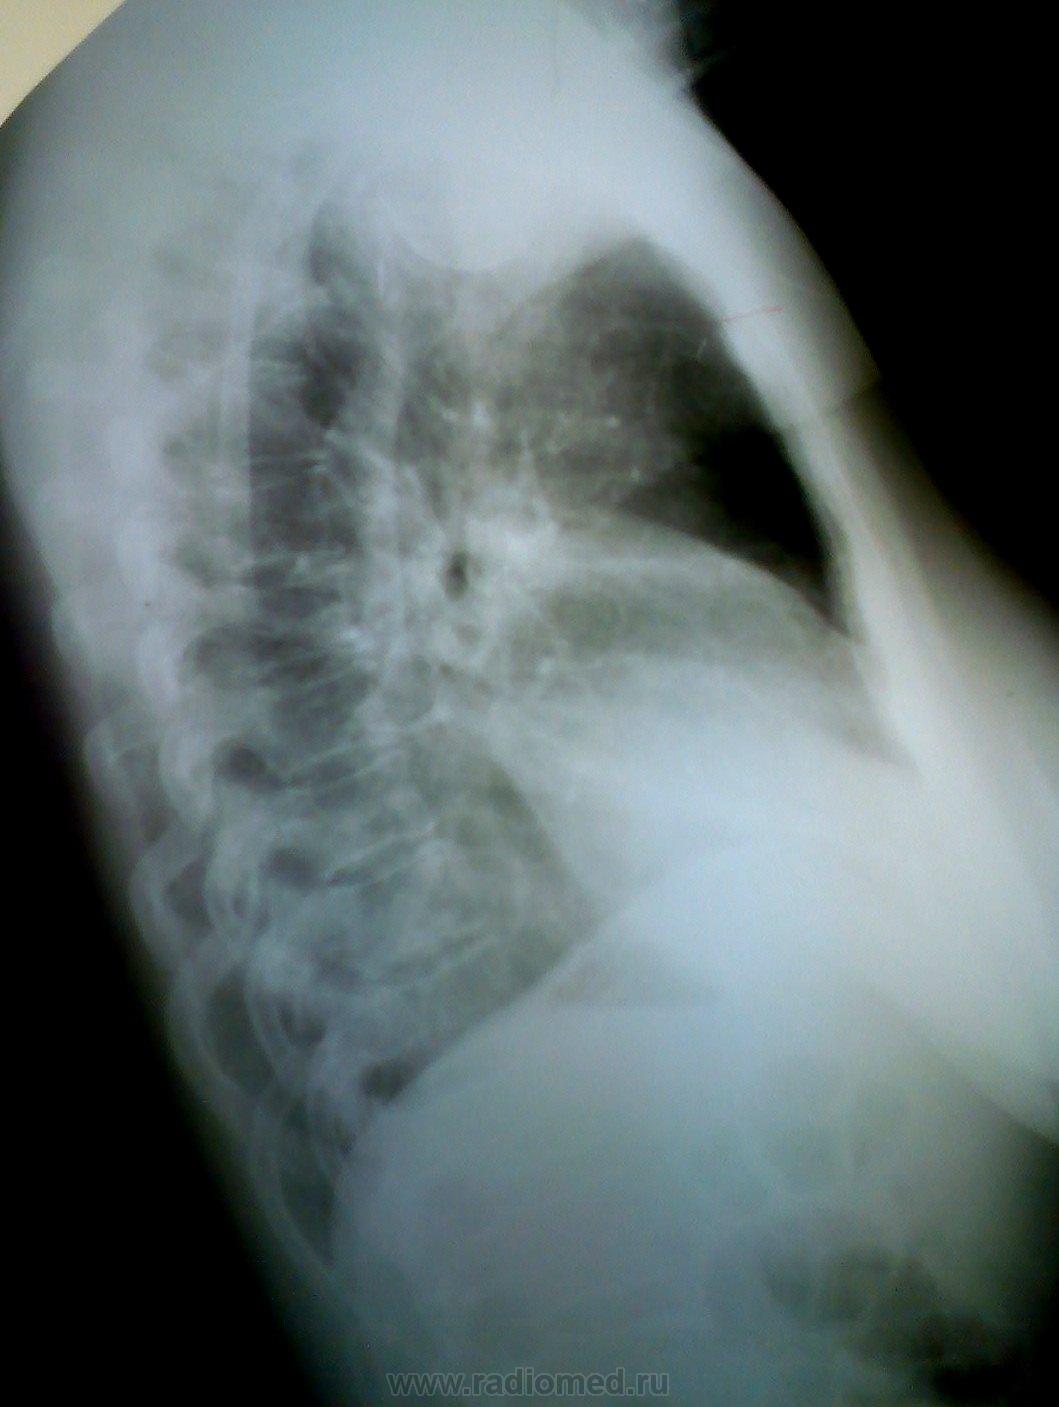

Описывая это "произведение" на следующее утро назначаю контроль, в т.ч. и грудной клетки в правой боковой проекции

Репродукции рентгенограмм нерезки, бронхов практически не видно..., думаю здесь ателектаз S7, S8.  возможно, с некоторым выпотом в главной междолевой щели.

Ателектаз средней доли (красный) + релаксация купола диафрагмы справа (зеленый) дали такое гомогенное интенсивное затенение. Валентин Львович, Вас не глючит. Больная, видимо, поела.

У меня пока, как рабочая версия, аденома среднедолевого бронха.

Поддерживаю Medea, объёмное уменьшение средней доли присутствует! За счёт чего (пневмофиброз/онко?) предстоит узнать на дообследовании.

А что сказать? Обструкция н/д (промежуточного) бронха правого л-го, причем с июня-месяца. На реконструкциях культя. ФБС.

Я не могу понять как могли сказать все нормально.... Наверное сказали, потому что уже ничего нельзя было сделать... Ателектаз нижней доли.

Потом (на след снимках)  видно уже произошел ателектаз нижней доли справа :(

На КТ- все явно видно. + слева в области корня тоже какой-тоинфильрат (на 1 скане вижу, что эт оо такое - надо покрутить). + медиастинальная лимфаденопатия.

ФБС. И ОД, Скорее всего поняли что ничего уже не сделаешь...  Правада я по нескольким акиалам про это не скажу (надо видеть все исследование). Вообщим мой бфы диагноз (по представленным сканам) был бы центральный с-r правого легокго + ателетаз нидней доли + мтс в медиастинальыне лимфоузлы (прходже и контрлатеральные) + мтс в противоположное легкое. Кончено, возможнг, увидев все исследование, я бы изменил мнение...

Ателектаз нижней и средней долей не вызывал у меня сомнения еще на первых рентгенограммах, да простит меня Медея за провокационные вопросы по поводу увеличения доли. Как тут не вспомнить лекции Михаила Абрамовича Гинзбурга.

Слишком явным были изменения, дабы уложить их только в плеврит.

Клинически сейчас только покашливание, небольшая потеря в весе, да СОЭ 65. Вот и все.

Не ухватись я за картину ателектаза, так и ушла бы она домой "покашливать".

Заключение практически слово в слово повторяет Ваше, только я добавил...ателектаз нижней и средней доли...

P.Sю Пересматриваю снимки- мда похоже аталектаз средней тоже. + гипервентиляция верхней (особенно на боковом впидно, как увеличено ретростернально епространвтсво и повышена его воздушность)

Да, гипервентиляция верхней доли справа очень показательна, как и симптом "кулис" по контуру атетектазированой части правого легкого.